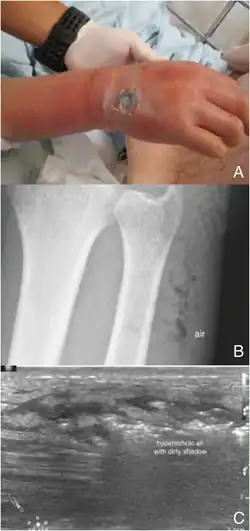

Point-of-care ultrasound (POCUS) may be useful in the diagnosis of NF if MRI and CT are not available.[18] It can also help rule out diagnoses that mimic earlier stages of NF, including deep vein thrombosis (DVT), superficial abscesses, and venous stasis.[18] Linear probes are generally preferred for the assessment, especially in the extremities.[18]

Findings characteristic of NF include abnormal thickening, air, or fluid in the subcutaneous tissue.[18] This can be summarized as the mnemonic "STAFF" (Subcutaneous irregularity or Thickening, Air, and Fascial Fluid).[18] The official diagnosis of NF using ultrasound requires "the presence of BOTH diffuse subcutaneous thickening AND fascial fluid more than 2 mm."[18] Gas in the subcutaneous tissue may show "dirty acoustic shadowing."[15] However, similar to other imaging modalities, the absence of subcutaneous free air does not definitively rule out a diagnosis of NF, because this is a finding that often emerges later in the disease process.[18]

Plain radiography (X-ray)

It is difficult to distinguish NF from cellulitis in earlier stages of the disease using plain radiography.[15] X-rays can detect subcutaneous emphysema (gas in the subcutaneous tissue), which is strongly suggestive of necrotizing changes. However, air is often a late-stage finding, and not all necrotizing skin infections create subcutaneous emphysema. Hence, radiography is not recommended for the initial diagnosis of NF.[15] However, it may be able to identify the source of infection, such as foreign bodies or fractures, and thus aid in subsequent treatment.[15]